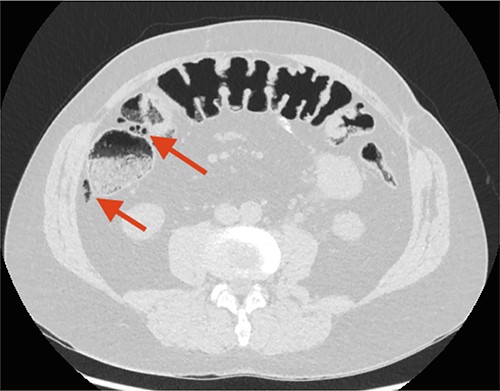

Two days later, the patient returned with intensified pain in the left flank, and a CT scan showed a calculi in the left ureter and progression in the free air located along the ascending colon (Fig. 2). The patient had no abdominal physical signs indicative of peritonitis, no fever and normal blood test.

CT scan performed 2 days after the first admission to the Emergency Department (ED). The arrow points at remaining FIA along the ascending colon/right flexure.